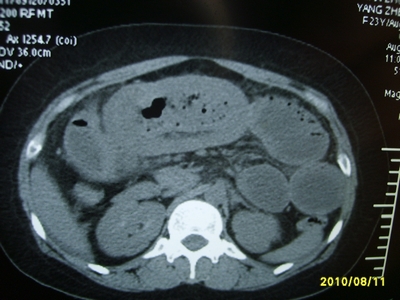

5天前突发腹痛剧烈难忍,伴解淡血水样便。近一天来腹痛缓解,没有明显的腹膜炎的体征。今天照的腹部ct。从ct上看感觉是一个绞窄性肠梗阻,但是现在没有腹痛。不好解释

高位肠梗阻(不全性),原因小肠(空肠)扭转,肠壁水肿增厚,成年人肠梗阻要排除合并占位,建议手术。

绞窄性肠梗阻_肠管套叠 扭转,肠壁明显水肿。

支持绞窄性肠梗阻,肠壁明显水肿并见有多发小泡状积气--肠坏死

考虑绞窄性肠梗阻并肠坏死。